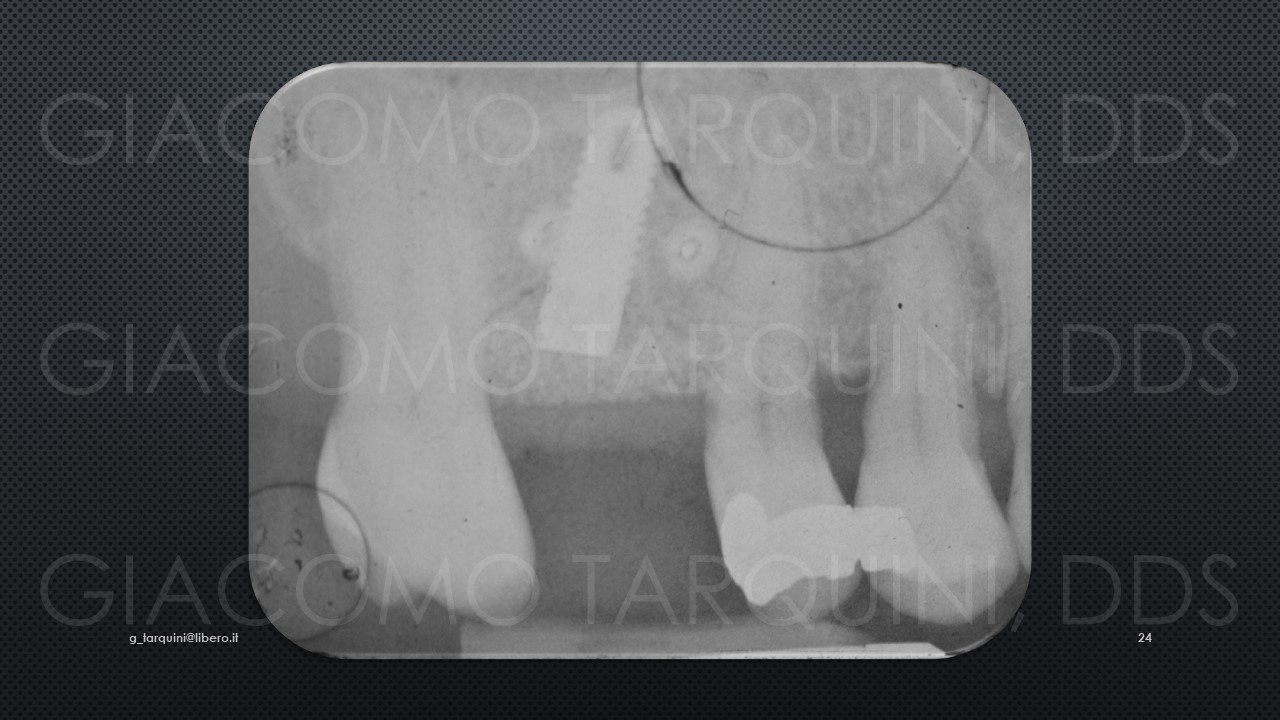

CASO CLINICO

Il caso clinico illustra una procedura di trattamento chirurgico-rigenerativo di una peri-implantite mediante decontaminazione effettuata con dispositivo «PIEZOCLEAN by Dr. Giacomo Tarquini»

Diapositiva24.thumb.JPG.d68c89b53ab23f812d2026319c155540.JPG